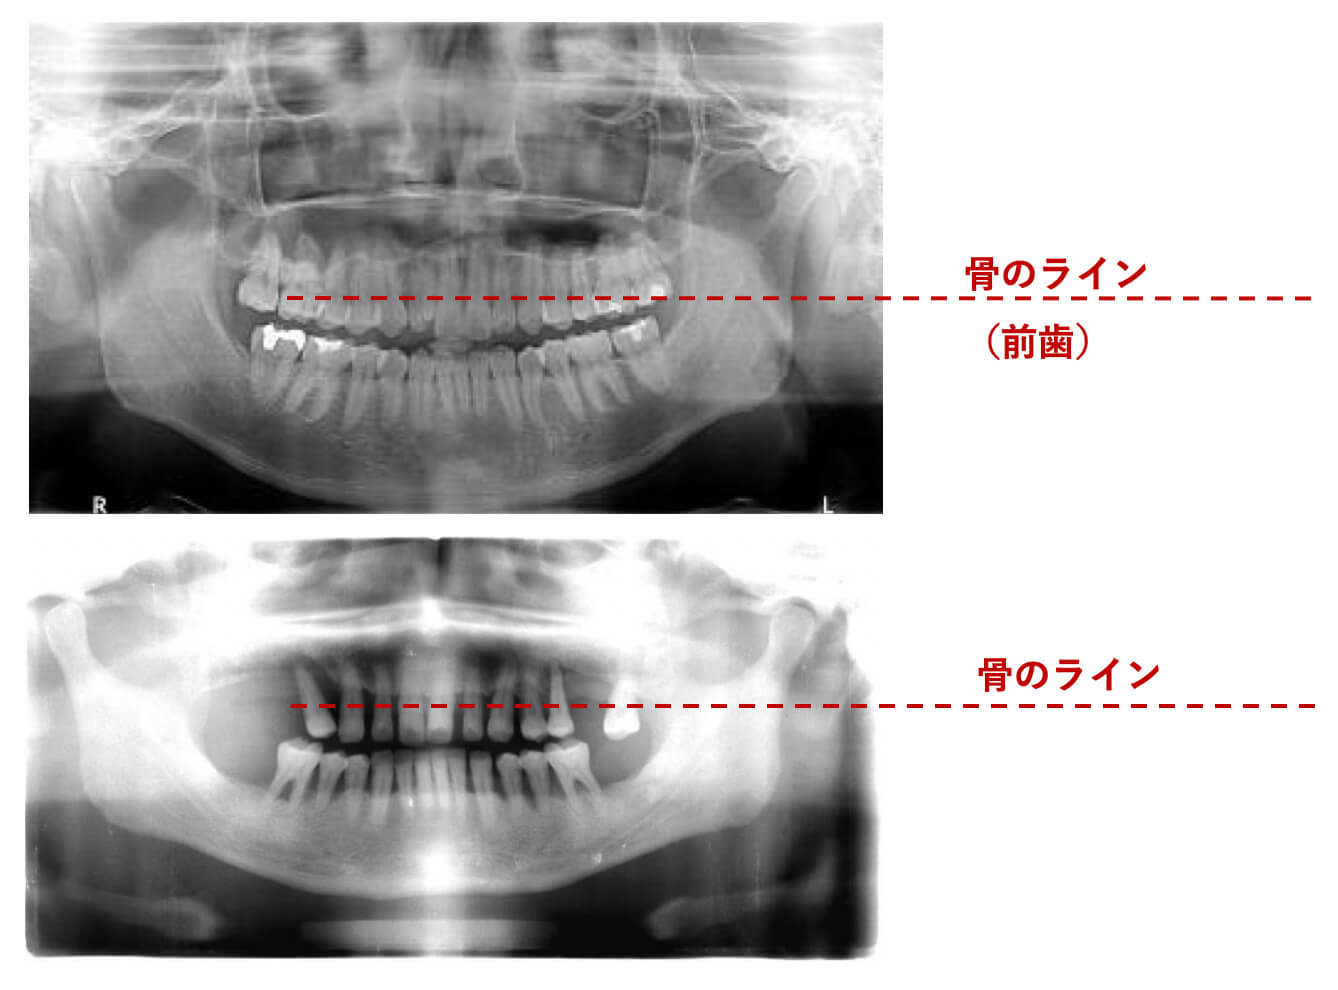

パノラマ写真での比較